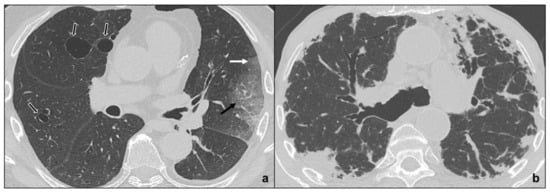

- Early phase/Stage 1 refers to days 0–4, and ground glass opacities represent the main radiological findings (Figure 1a);

- Progressive phase/Stage 2 refers to days 5–8, and the hallmark is represented by crazy paving pattern (Figure 1b) coexisting with extensive ground glass opacities and initial consolidative foci;

- Peak phase/Stage 3 is typical of days 9 to 13, and CT shows consolidations (Figure 1c), sometimes surrounded by a ground glass halo (halo sign);

- Absorption phase/Stage 4 starts around day 14, and ground-glass areas together with linear consolidations are appreciable (Figure 1d).